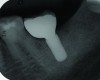

Peri-implant diseases present in two forms—peri-implant mucositis (Figure 1 and Figure 2) and peri-implantitis (Figure 3 and Figure 4). Both involve an inflammatory reaction in the tissues surrounding an implant—ie, bleeding on probing and/or suppuration; probing depths usually exceed 4 mm.1,3 However, when there is also bone loss present beyond the physiologic remodeling that may occur after implant placement, a diagnosis of peri-implantitis should be made, as this condition, when compared to mucositis, is far more serious and difficult to resolve.4

The authors believe, in accordance with the American Academy of Periodontology’s whitepaper,21 that clinicians should obtain radiographs that establish baseline bone levels both at the time of implant placement and immediately following final prosthesis insertion to facilitate comparison. They should also be taken at the first signs of disease that could signal bone loss, including change in tissue tone and color, bleeding, purulence, and increased or increasing probing depths—all of which should be evaluated at every visit.21